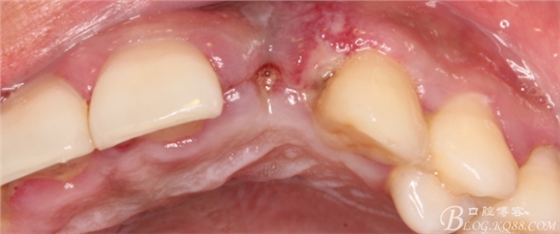

10天拆線一切正常,又過了兩周患者復(fù)診,自述期間無異常。口內(nèi)檢查,真的嚇了一跳,唇側(cè)鼓了個(gè)包,擠壓有白色分泌物溢出,絕對(duì)不是膿液,液體排除后,術(shù)區(qū)觸診空虛,外觀塌陷。這時(shí)候考研大夫的時(shí)刻到了,是先觀察一段時(shí)間再說?還是馬上進(jìn)行處理?我的回答是:馬上處理!如果你沒有及時(shí)處理,而是放患者回家觀察,那么接下來會(huì)發(fā)生如下情況:1.回家后患者家屬及親友會(huì)有很多你可以想象得到的討論;2.患者及家屬會(huì)對(duì)你產(chǎn)生不信任,勢(shì)必會(huì)到其他門診或醫(yī)院檢查,他院大夫會(huì)不會(huì)發(fā)表對(duì)你不利的言論;3甚至?xí)蚁嚓P(guān)法律界人士找你討要說法。

于是我果斷告知患者,手術(shù)失敗了,不能拖延,如不及時(shí)處理,炎癥繼續(xù)發(fā)展會(huì)很快波及鄰牙牙槽骨。患者接受我的建議。切開翻瓣,骨粉及生物膜消失了,骨吸收嚴(yán)重,幸運(yùn)的是,因?yàn)樘幚砑皶r(shí),鄰牙骨支持依然存在。